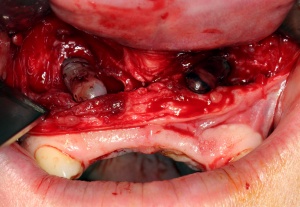

Im August 2012 erfolgten die 3D-gestützte Implantation (6 Implantate, Firma Nobel Biocare, System Active) im Oberkiefer mit Bone Split sowie eine An- und Auflagerungsosteoplastik vom linken Beckenkamm im Unterkiefer nach Entfernung der Miniimplantate (Abb. 3). Nach komplikationsloser Einheilung wurde im Dezember 2012 die Materialentfernung und Implantation im Unterkiefer (6 Implantate, Firma Nobel Biocare, System Active) durchgeführt (Abb. 4). Die Osseointegration verlief ungestört. Aufgrund der ungenügenden Weichgewebssituation im Unterkiefer erfolgte an jedem Implantat bei Freilegung eine Vestibulumplastik mit Einlagerung einer bioresorbierbaren Membran (Firma Botiss, Mucoderm, Abb. 5 und 6). Die endgültige prothetische Versorgung erfolgte durch den truppenzahnärztlichen Kollegen in der Stammeinheit des Patienten (Zahnarztgruppe Nordholz / SanZ Celle) mit einer gaumenfreien implantatgetragenen Teleskopprothese im Ober- und Unterkiefer, die eine festsitzend-herausnehmbare vollständige stomatognathe Rehabilitation des Patienten ermöglichte (Abb. 7 und 8). Er wurde zum halbjährlichen Recall angehalten.

Zum Ausgleich der konsekutiv vorliegenden Weichgewebsatrophie erfolgte im Juni 2012 nach Genehmigung des Antrags durch das Sanitätsamt der Bundeswehr zunächst die Implantation von 2 Weichgewebsexpandern (Firma Osmed) im Oberkiefer (Abb. 10). Nach Schaffung eines adäquaten Weichgewebsbettes wurde im Juli 2012 zur Korrektur der extremen Hartgewebsatrophie eine Augmentation vom Beckenkamm durchgeführt (Abb. 11). Im Dezember 2012 erfolgten in Lokalanästhesie nach ungestörter Einheilung die Materialentfernung der Osteosyntheseschrauben und die Implantation von 4 dentalen Implantaten (Firma Nobel Biocare, Replace straight, Abb. 12). Durch Atrophie und die rekonstruktiven Operationen bedingt, wurde zur Korrektur der ungenügenden Weichgewebsverhältnisse eine Vestibulumplastik nach 3 Monaten mit Einlagerung einer bioresorbierbaren Membran (Firma Botiss, Mucoderm) durchgeführt. Nach weiteren 3 Monaten erfolgte die Freilegung der Implantate (Abb. 13) mit einer Rolllappenplastik an jedem Implantat zur vestibulären Rekonturierung der Schleimhaut.